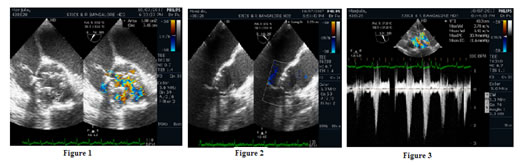

After coming off cardiopulmonary bypass the aortic valve coapted well and appeared like a standard tri-leaflet repair. After bypass, the leaflets opened and coapted well with no residual leak. Postoperative average peak gradient was 17.6 ± 9.75 mm of Hg. Postoperative average mean gradient was 8.85 ± 6.48mm of Hg. Two cases had gradients higher than mean and peak gradients of 15 and 30 mmHg (respectively). One case had a peak gradient of 30mm of Hg and mean gradient of 14mm of Hg. No patient left the operating room with an aortic regurgitation (AR) grade of 2 or greater. Postoperative average left ventricular ejection fraction was 50.95 ± 9%.

Figure 1: ME Aortic valve short axis view of the reconstructed valve post Ozaki’s procedure –Planimetry of the valve area; Figure 2: ME Aortic valve long axis view of the reconstructed valve post Ozaki’s procedure- Coaptation Height measurement; Figure3: TG Aortic valve long axis view of the reconstructed valve post Ozaki’s procedure – Aortic valve gradient measurement.